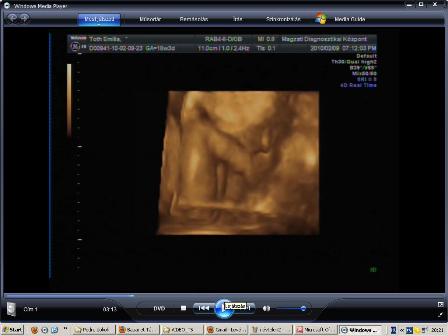

Végre sikerült bescannelnem a múltkori 2D-s UH képet.

Kép

Látszik szemből a pofija...az egyik kezecskéje a mellkasa mellett, míg a másikkal fogja a fülét, és látszik a könyöke. :)